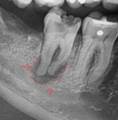

3 |

Quiste radicular |

Imagen radiolúcida, redonda u ovalada y unilocular, que se presenta en la región periapical y puede estar rodeada por hueso cortical delimitada por una línea radiopaca continua lo cual indica la existencia de hueso esclerótico.3,7 |

|

|||

4 |

Quiste dentígero |

Lesión

unilocular, asintomática, radiolúcida, caracterizada por márgenes

escleróticos bien definidos y asociada con la corona de un diente sin

erupción.8 |